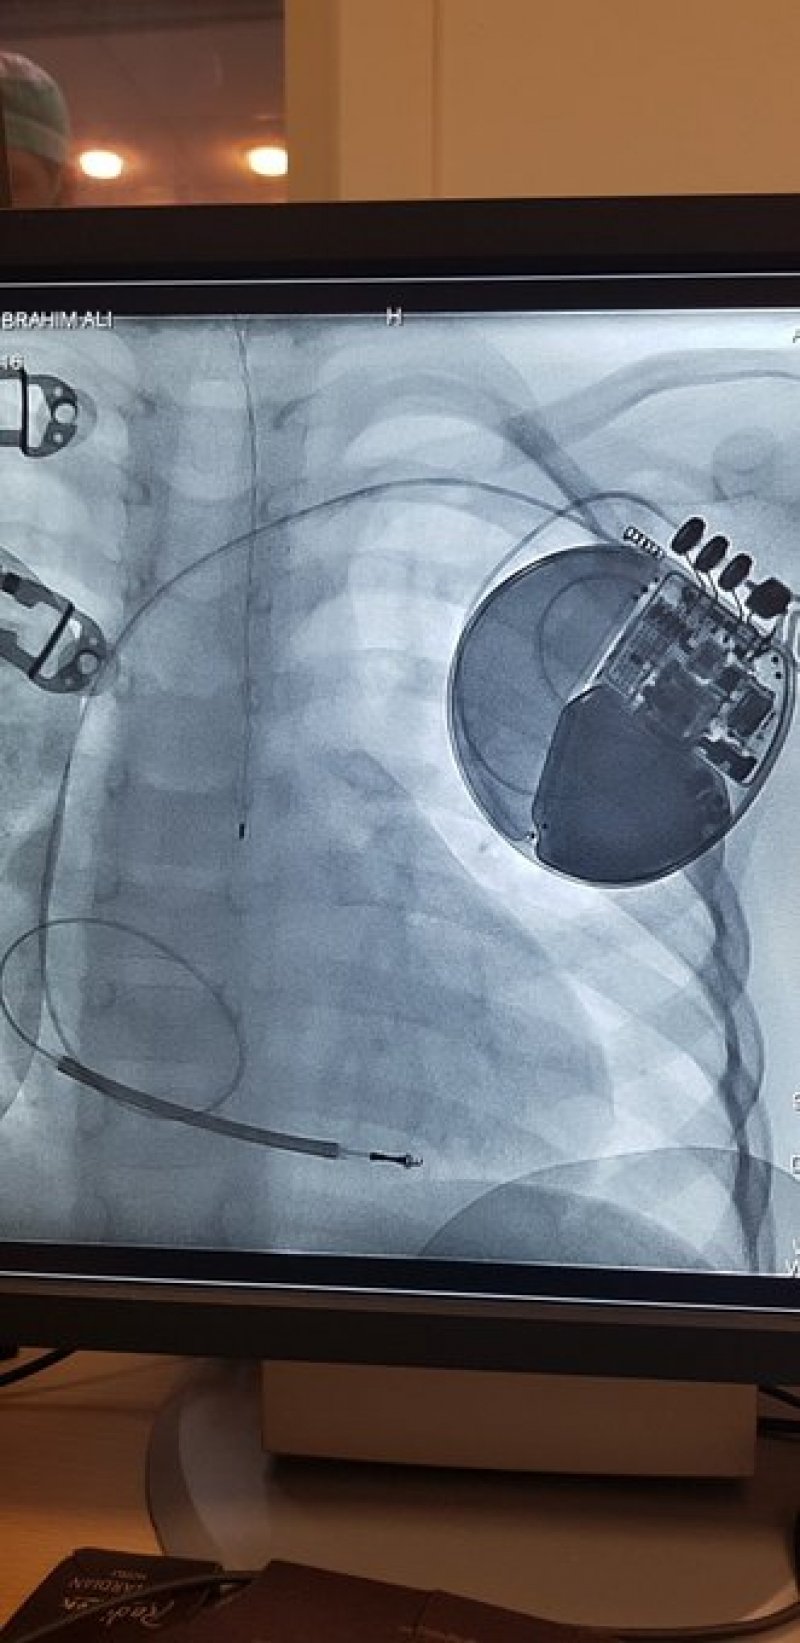

منذ بضعة أيام أصبح الطفل إبرهيم أصغر مريض يضع جهاز تنظيم ضربات القلب، كُتبت له الحياة ونهاية سعيدة بعدما واجه الموت. ما جرى يستحق التوقف عنده، فهذه الجراحة تعتبر الأولى في لبنان والمنطقة، فكيف أُنقذ، وماذا في التفاصيل؟

وفق شرف الدين، أنه "إجمالاً، يوضع جهاز منظم ضربات القلب لطفل يزن أكثر من 25 كيلوغراماً، ولكن إبرهيم كان يزن فقط 15 كلغ ونتيجة تعذر وجود أجهزة متخصصة تلزم للجراحة لهذا العمرفي لبنان، اضطررنا إلى وضع الجهاز عبر التمييل ليصبح أصغر مريض يضع هذا الجهاز في لبنان والمنطقة. وبالرغم عدم توافر المواصفات المطلوبة، لا يسعنا سوى القول "الحمدالله على كل شيء، ولقد عاد إبرهيم إلى عائلته ومنزله ".